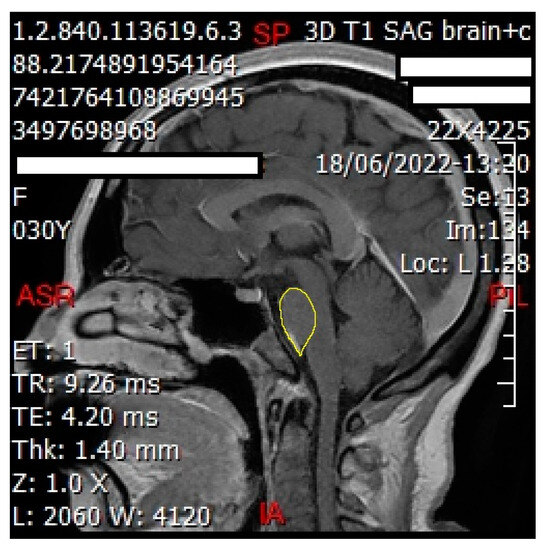

2.6. Grayscale Measurement

We employed ImageJ Fiji Software (Version 1.53q) to quantify the grayscale intensities of both the pituitary gland and the pons. After verifying sagittal sections containing the pituitary gland (Figure 2 and Figure 3) with a certified radiologist, we delineated its borders using the ‘Freehand Selections’ tool. Within the ‘Analyze’ tab, histograms were generated for each section, providing mean and standard deviation values of grayscale intensities. Using SPSS 25 (Statistical Package for the Social Sciences, IBM, Armonk, NY, USA), we calculated the overall mean and standard deviation across all sections for both the pituitary gland and the pons (mean and standard deviation from each section). The same methodology was applied to analyze the grayscale intensities of the pons (Figure 4 and Figure 5), ensuring consistency for normalization purposes. The normalized grayscale intensity was determined by dividing the mean grayscale intensity across all sections of the pituitary gland by that of the pons.

Figure 2. Sagittal cut of the brain showing delineation of the pituitary gland (shown in yellow line) to obtain the grayscale using ImageJ Fiji Software. This technique was performed for each sagittal cut involving the pituitary gland for each patient.